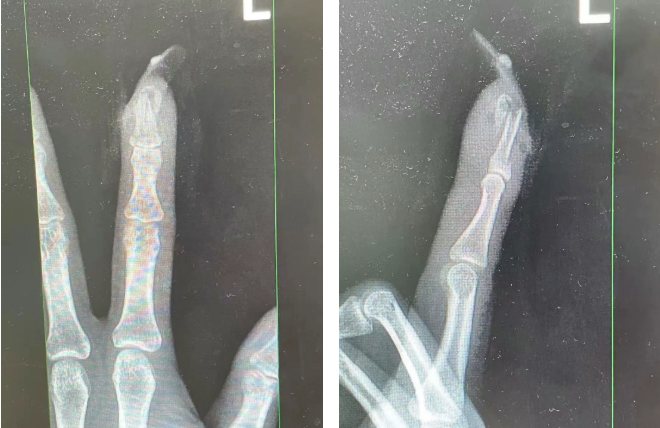

經(jīng)檢查

王女士指甲斷裂

部分甲床外露

醫(yī)生表示如果沒有美甲

傷害不會這么嚴重

王女士受傷手指的X光影像。圖源:杭州市臨平區(qū)中西醫(yī)結合醫(yī)院